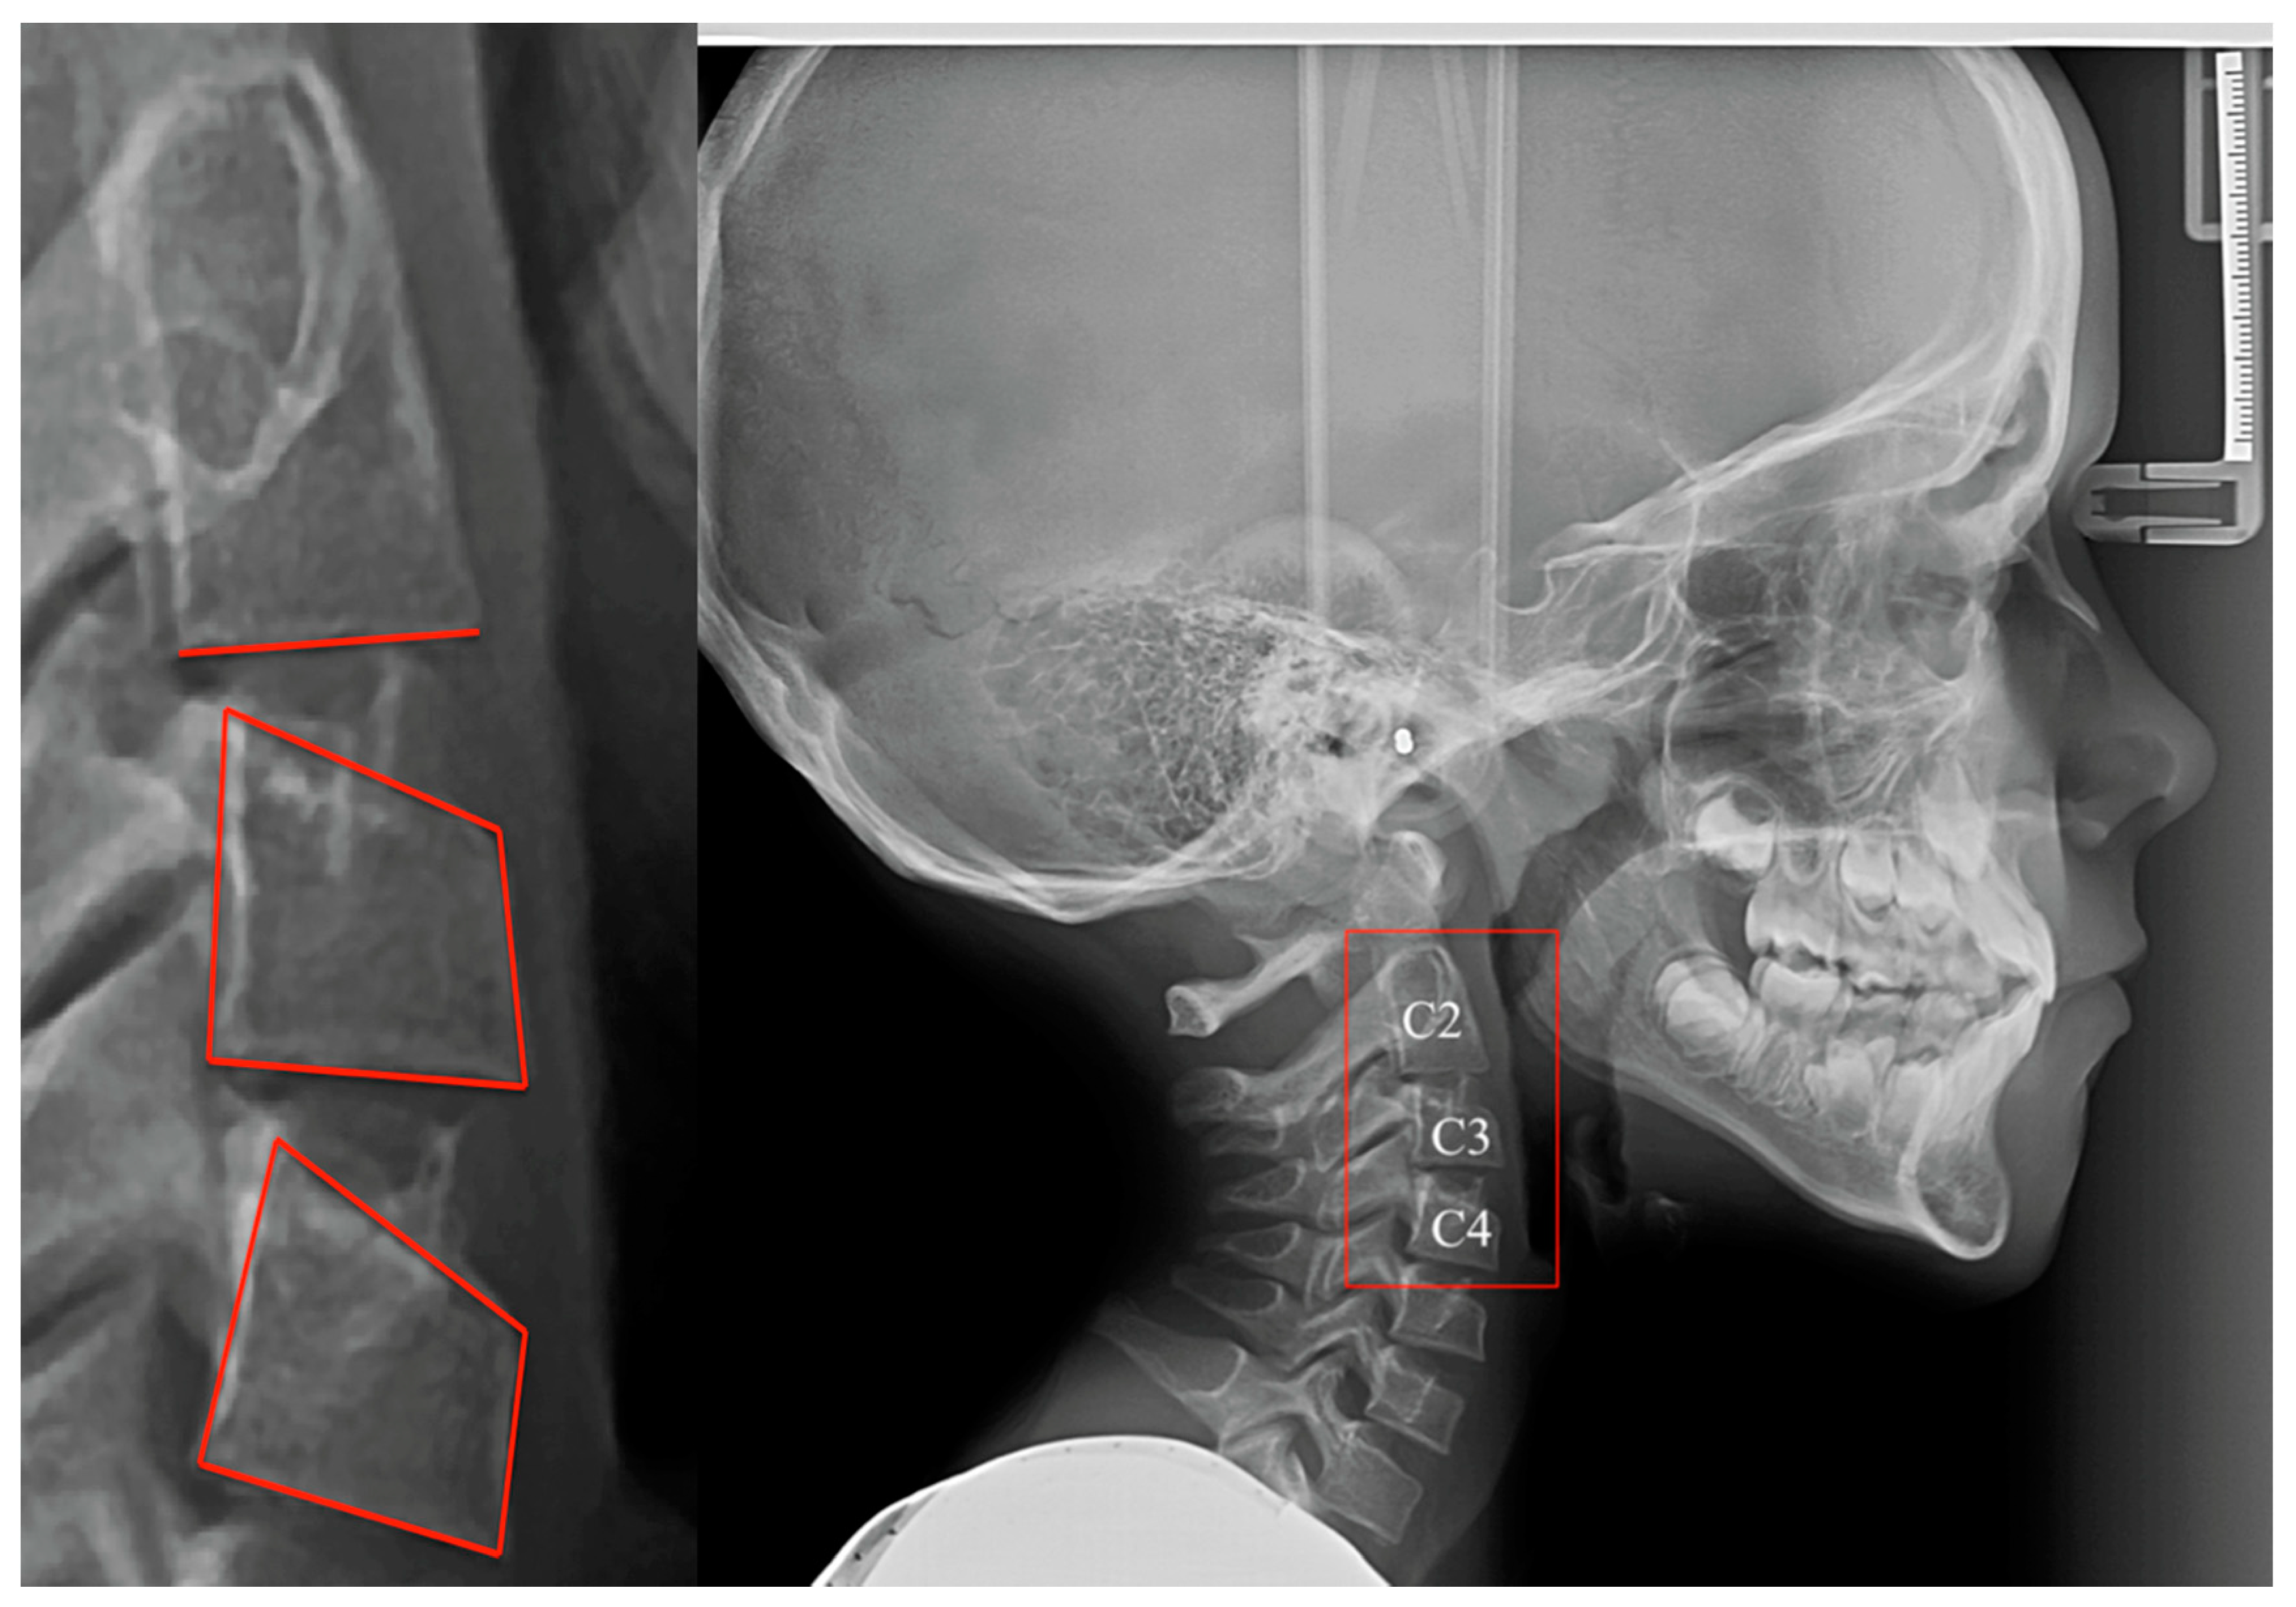

The radiological aspect of the cervical vertebrae can be used to estimate the degree of bone development. The method based on the investigation of cervical vertebrae has undergone several changes over time [9,10] and is currently known as the Cervical Vertebral Maturation (CVM) method. It involves the examination of cervical vertebrae 2, 3, and 4 on a lateral cephalometric radiograph [11]. Lateral cephalometric radiographs are necessary for establishing the diagnosis and treatment plan in orthodontics. Therefore, the assessment of skeletal maturity is possible, without any need for additional irradiation [12]. Further studies need to be conducted in order to find associations between age and CVM developmental stages.

For the assessment of skeletal maturity, the CVM method was used, as described by Baccetti et al. (2005). The CVM method consists of six different maturation stages (from CS1 to CS6), according to different morphological features of cervical vertebrae 2, 3, and 4. The inferior border of the three cervical vertebrae must be investigated, as well as the shape of the third and fourth cervical vertebrae [11].

The CVM method was applied on lateral cephalometric radiographs, available in a digital format, by examining the morphological changes of the cervical vertebrae and comparing them with the different developmental stages (Figure 1). In order to avoid inter-operator bias, the examination was performed by a single investigator (M.A.E.).

Figure 1. Lateral cephalometric radiograph with the 2, 3, and 4 cervical vertebrae highlighted.